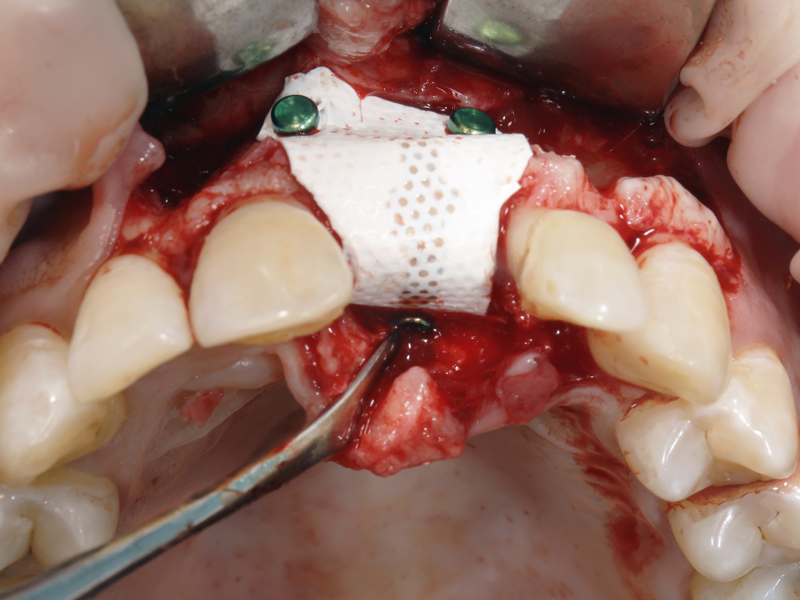

Guided Bone Regeneration (GBR):

Bei diesem Verfahren wird um das Implantat oder die Defektstelle eine Membran angelegt, die das Wachstum von Knochengewebe fördert, während sie gleichzeitig das Eindringen von Weichgewebe in den Bereich verhindert. Dies unterstützt das Wachstum von neuem Knochenmaterial.